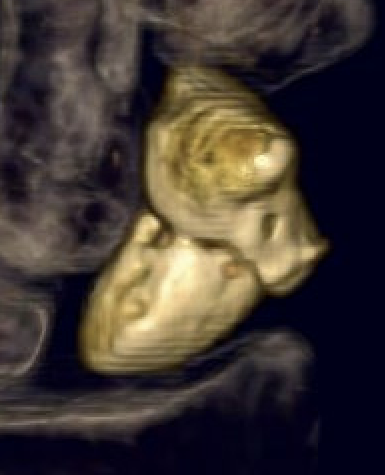

CT

Indication

- diagnose nonunion and identify size of cyst / defect

- identify humpback deformity

- helps to plan approach / size and shape of bone graft

Failure of fracture to unite at 3 months on CT scan

Nonunion with flexion / humpback deformity

Nonunion with flexion deformity